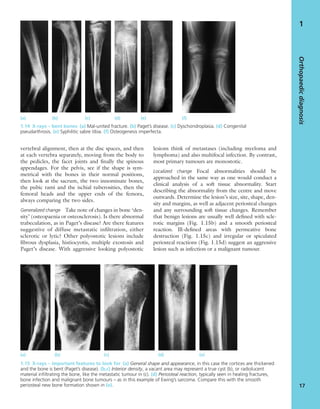

tion or fibrosis following ischaemic necrosis

(Volkmann’s ischaemic contracture).

4. Muscle imbalance Unbalanced muscle weakness or

spasticity will result in joint deformity which, if not

corrected, will eventually become fixed. This is